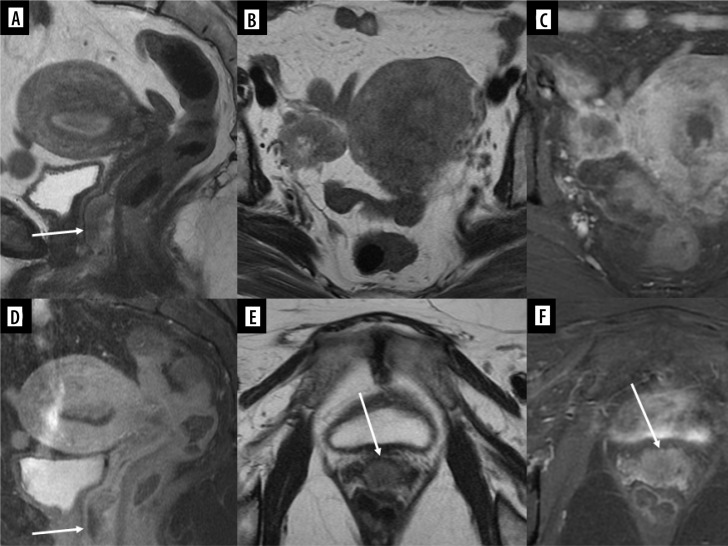

报告了四例软组织或骨肉瘤转移到生殖系统或乳房的女孩病例。其中两名患者的四肢横纹肌肉瘤(RMS)转移至乳房,一名患者的足部横纹肌肉瘤转移至卵巢,一名患者的骶骨软骨肉瘤转移至子宫静脉丛。在每个病例中,转移灶的外观都通过不同的成像方法显示出来:超声波、磁共振成像和计算机断层扫描。全面的文献回顾证实,只有少数病例描述过女孩软组织和骨肉瘤转移到本文主要关注的部位,尤其是生殖器官。尽管这种类型的转移很少发生,但在区分来源时,仍应考虑上述恶性肿瘤。这些罕见的临床情况被编织成一篇关于恶性肿瘤转移到生殖器官和乳房的综述。

Four cases of girls with metastases of soft tissue or bone sarcomas to the reproductive system or breasts are reported. Two patients had metastases to the breast from rhabdomyosarcoma (RMS) of the limbs, one had metastases to the ovary from RMS of the foot, and one had metastases to the uterine venous plexus from chondrosarcoma of the sacrum. In each case, the appearance of metastases was shown in various imaging methods: ultrasound, magnetic resonance imaging, and computed tomography. A thorough literature review confirmed that only a few cases of soft tissue and bone sarcoma metastasis to the locations of primary interest of this article in girls have been described, especially in the context of reproductive organs. Despite the rare occurrence of this type of metastases, the malignant tumours mentioned above should be considered when differentiating the source. These rare clinical situations are woven into a review of malignant neoplasms' metastases to the reproductive organs and breast.